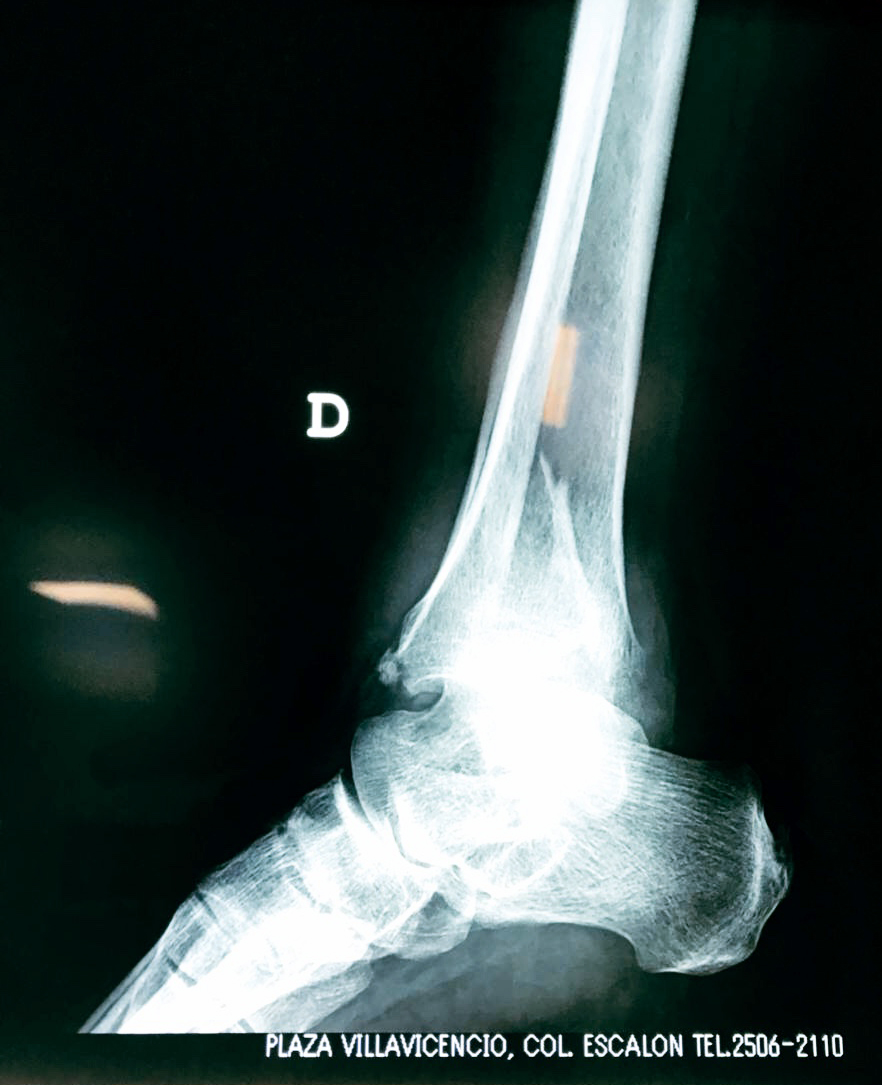

Una fractura de tobillo es la rotura de uno o más de los huesos del tobillo. Estas fracturas pueden ser:

Algunas fracturas de tobillo pueden requerir cirugía si:

- Los extremos de los huesos están desalineados entre sí (desplazados).

- La fractura se extiende hasta la articulación del tobillo (fractura intra-articular).